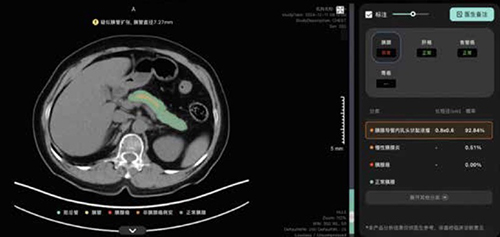

丽水中心医院放射科医生利用AI比照查看病人CT

大模型提示胰腺肿瘤风险